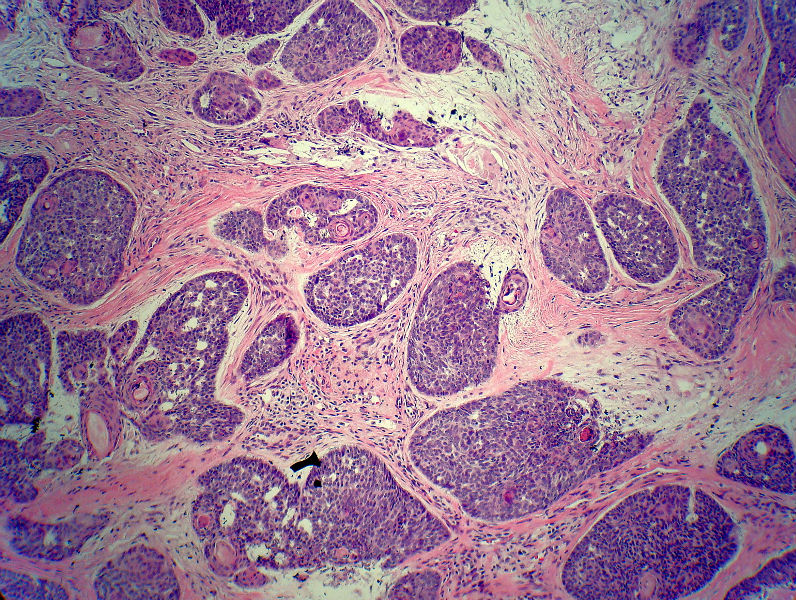

男,49岁,后枕部肿物3年,偶有破溃出血。

大体:皮肤半球形隆起,大小约2.3×2厘米,高出皮表0.8厘米,切面灰白,质地细腻。